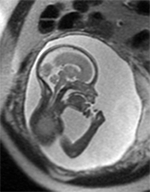

The Baby Brain Research Group studies how newborns' brains get injured and what the best diagnostic tools are to see that injury early on. Our aim is to see brain injury early enough so we can develop treatments to reduce the damage and aid recovery of injured areas. We also hope to identify those children whose long-term development will be affected, and who could benefit from early therapy.